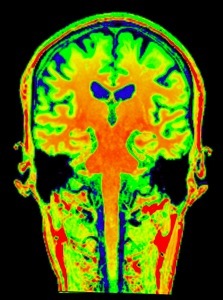

plan coronal

plan coronal